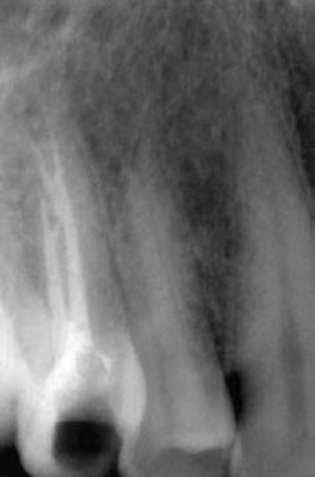

После звукового сигнала извлекают обтуратор из печки. Необходимо прицелиться и прямолинейно, без излишнего давления, за 2-3 с погрузить обтуратор до стоп-отметчика. Если все благополучно, то необходимо носитель отсечь на уровне устья специальным бором Therma-Cut (рис. 40-14).

pic 0344

Рис. 40-14. Рентгенограммы. Корневые каналы обтурированы с помощью системы Soft Core.